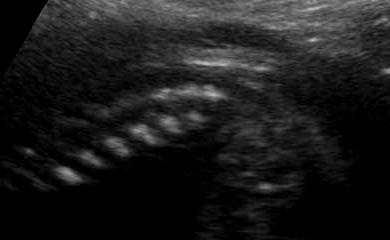

E' caratterizzata da deficit di vario grado di tutti e quattro gli arti (assenza di ulna e fibula con assenza o deficit severo degli arti come focomelia, oligodattilia, etc.), con ipoplasia o agenesia delle ossa del bacino (anche ipoplasia o agenesia del sacro), anomalie genitali consistenti in agenesia dell'utero e della vagina, micropene.

La diagnosi ecografica si basa principalmente sulle anomalie degli arti  e sull'agenesia del sacro.